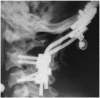

Methods: Upper cervical lesions in nine patients undergoing hemodialysis were surgically treated. Mean age at surgery was 61.6 years (range, 52-68 years), and the mean follow-up period was 45.4 months (range, 2-98 months). Patients had undergone hemodialysis for an average of 25.3 years (range, 16-40 years) at surgery. Seven patients with destructive spondyloarthropathy (DSA) of the upper cervical spine were treated with atlantoaxial or occipitocervical fixation. Two patients with retro-odontoid pseudotumors were treated with C1 posterior arch resection alone. Japanese Orthopedic Association (JOA) scores for cervical myelopathy, postoperative complications, postoperative radiography, and preoperative and postoperative occipital pain were evaluated.

Results: Mean preoperative and postoperative JOA score was 3.7 and 8.1, respectively. The seven patients with DSA had severe preoperative occipital pain that disappeared postoperatively. Postoperative radiography showed solid bone union in DSA cases and no instability in pseudotumor cases.